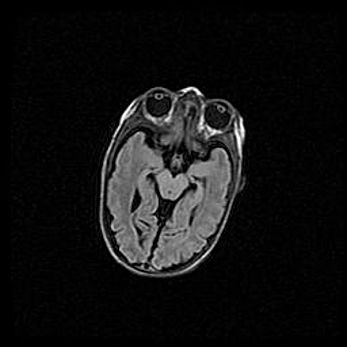

Открытая гидроцефалия.

Возраст: 9 месяцев 12 дней

Вес: 6800 г

Пол: мужской

Окружность головы: 41,5 см

Срок гестации: 28 недель

Гидроцефалия головного мозга у новорожденных имеет характерный признак: опережающий рост окружности головы приводит к визуально хорошо определяемой гидроцефальной форме сильно увеличенного в объёме черепа. Детские неврологи определяют следующие симптомы гидроцефалии у грудничков: выбухающий напряжённый родничок, частое запрокидывание головы, смещение глазных яблок к низу.